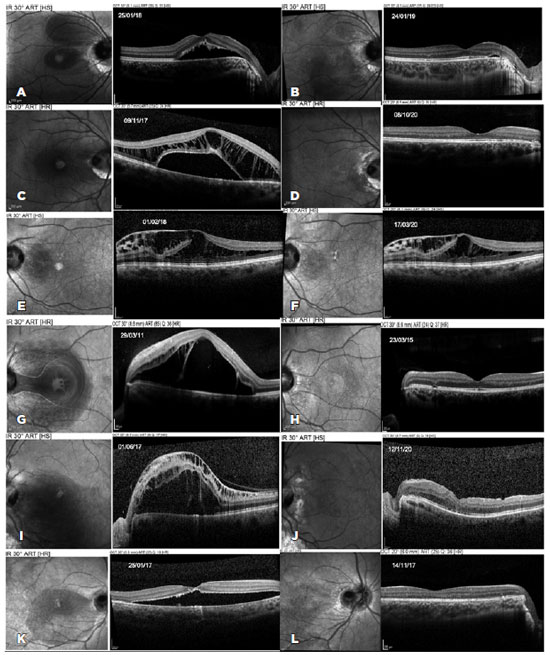

Postoperatively, OCT demonstrated complete fluid resolution in five patients, without recurrence during follow-up (Figure 1). Total reabsorption was documented after 12 months, 13 months, 25 months, and 6.5 months in patients number 1, 2, 4, and 6, respectively. Patient number 5 failed to demonstrate fluid reabsorption on OCT and underwent pars plana vitrectomy, achieving complete fluid resolution 41 months after the initial treatment. Patient number 3 failed to demonstrate progressive fluid reabsorption and refused any additional treatment.

08-fig01tb.jpg)

Clinical examination of patient number 4 showed a possible optic disc pit in the right eye (contralateral eye), which was confirmed on OCT (Figure 1). Cases of optic disc pit not associated with maculopathy should not be treated prophylactically with laser along the temporal optic disc margin. The natural history of this disease may not involve maculopathy development, and the risk of injury to the papillomacular bundle does not justify this approach(2).